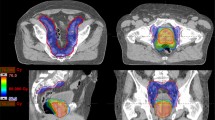

As published before, radiotherapy was delivered with IG-IMRT or IG-VMAT in 33 fractions with SIB and two dose levels of 1.82 and 2.31 Gy per fraction, resulting in a prescribed PTV dose of 60.06 Gy (D95) and a PTVBoost mean dose of 76.23 Gy. 32 fractions were applied only in patients with low-risk prostate cancer in 44 cases. For pelvic lymphatic radiation, the prescribed dose was 45.5 Gy (D95) with 1.82 Gy per fraction. A CTVP−SV was generated consisting of the prostate and the base of the seminal vesicles, whereas CTVP+SV included the prostate and the seminal vesicles. PTVBoost was defined by a 5-mm margin around CTVP−SV with avoidance of the rectum. The PTV was created by a 10-mm margin around CTVP+SV in all but the dorsal direction, where a 7-mm margin was used. Pinnacle3 (Philips Radiation Oncology Systems, Fitchburg, WI, USA) was used for treatment planning. More information on target volume definition, treatment planning, and treatment delivery has been described before [11, 12].

This report differs from other studies, as a simultaneous integrated boost was used and the high-dose PTV was restricted to the prostate +5-mm margin with avoidance of the rectum. The low-dose PTV (margin of 10 mm, 7 mm towards posterior) was covered by the 60 Gy isodose. To ensure precise application, an integrated offline/online protocol of volumetric cone beam CT-guided radiotherapy was strictly implemented at our institution [11, 27,28,29,30]. Accurate positioning with daily IGRT contributes to improved tumor control and minimizes dose deviations [31,32,33], which is especially important for small PTV margins in high-risk disease with possible microscopic extracapsular extension [34]. Our patient distribution is comparable to the Austrian-German dose-escalation trial (74 Gy for intermediate- and high-risk patients) published by Goldner et al. using 3D conformal radiotherapy [35]: while GU and GI toxicity (grade ≥2) were higher (34 and 30%), 5‑year bRFS seemed inferior (80% intermediate, 60% high risk) to our study. This underlines both the importance of technical advances (IMRT and IGRT) and of high effective doses.